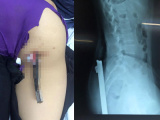

25/04/2019 02:21Nam sinh lớp 4 nhập viện vì bị bút chì dài gần 20cm đâm sâu vào mông

Vào ngày 19/4, nam sinh D. (đang theo học lớp 4, một trường tiển học trên địa bàn TP Hà Nội) phải nhập viện trong tình trạng chiếc bút chì dài gần 20cm đâm sâu vào phần mông phải, ngay gần hậu môn.

Sau khoảng 10 tiếng từ khi tiếp nhận, cuộc phẫu thuật diễn ra thành công với sự phối hợp của nhiều chuyên khoa khác nhau. Hiện nam học sinh này đã được xuất viện.

Theo bác sỹ Liên, may mắn tổn thương do bút chì đâm từ dưới lên không vào mạch máu lớn và không ảnh hưởng quá nhiều đến trực tràng, bàng quang của bệnh nhân. Sau phẫu thuật nam sinh này gần như bình phục hoàn toàn.